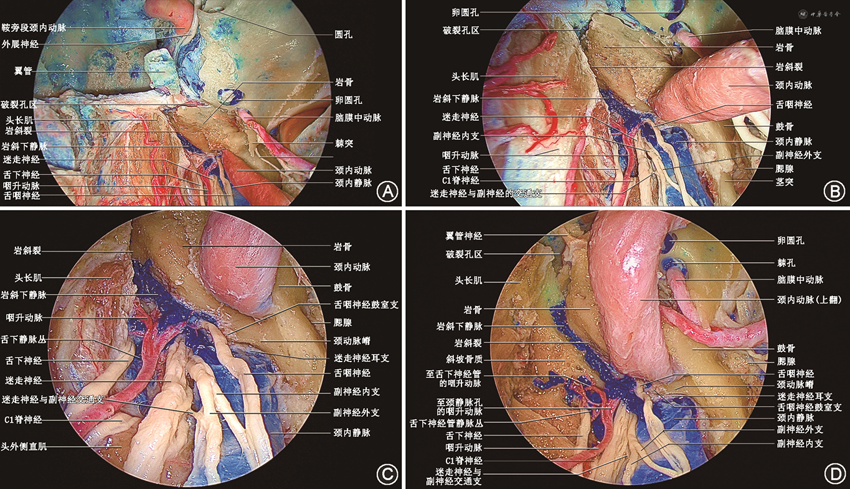

内镜经口侧颅底手术主要通过口腔宽大的自然通道到达侧颅底并处理侧颅底病变。腭构成固有口腔的顶,分隔鼻腔及口腔,经口入路做硬腭黏骨膜瓣时,应注意保护软腭、硬腭黏骨膜瓣的血供。侧颅底各分区解剖复杂,经口入路视角(图2)与颞下窝入路有所区别,熟悉内镜经口入路下的解剖结构是开展内镜经口侧颅底手术的前提。

3. 神经血管区:在咽鼓管区后方,由颈内动脉管外口、颈静脉孔、舌下神经孔和茎乳孔共4个颅底孔道构成。经颞骨岩部的颈动脉管外口进入颈动脉管。内镜经口入路中,可借助咽鼓管和腭帆提肌定位颈动脉管外口。

2. 内镜经口经翼下颌皱襞入路(侧方入路):内镜经口经翼下颌皱襞入路适用于病变主体位于侧方咽鼓管区和神经血管区的病变[5, 6],如咽后淋巴结、咽旁间隙肿瘤等。该入路的切口位于翼下颌皱襞内侧黏膜,进一步切开咽上缩肌后进入咽旁前间隙。定位咽旁段颈内动脉是内镜经口经翼下颌皱襞入路的核心。茎突咽筋膜位于茎突至咽上缩肌的三角区域,去除茎突咽筋膜,从内向外依次可见头长肌、咽升动脉、颈内动脉和颈内静脉。腭帆提肌位于该入路术腔的上部,其外上方的附着点位于颈内动脉外口前方,可作为颈内动脉外口定位的标志(图5)。

3. 内镜经口翼突后入路(联合入路):内镜经口翼突后入路适用于病变广泛侵犯颅底中线区域和侧方区域的病变,如晚期的复发性鼻咽癌、颅底恶性肿瘤等。该入路经口行大问号切口。切开咽上缩肌进入咽旁间隙,通过茎突肌群定位咽旁段颈内动脉,确定安全边界。在经鼻入路中,需要磨除翼突才能自前向后显露上述解剖结构。而在内镜经口翼突后入路中,在翼内肌和咽上缩肌之间通过下咽旁间隙至翼突后,从翼突后方即可显露上述解剖结构。避开翼突,通过咽旁间隙这一固有解剖间隙直达颅底,不仅创伤小、出血少、省时省力,而且因为保留了翼内肌和翼外肌,可以最大化地保护患者的咀嚼功能。该入路以最直接的径路到达岩斜区、颈静脉孔区,在确保风险可控的前提下,可以最大范围地显露岩斜区和颈静脉孔区,同时最大程度地保护翼内肌和翼外肌(图6)。